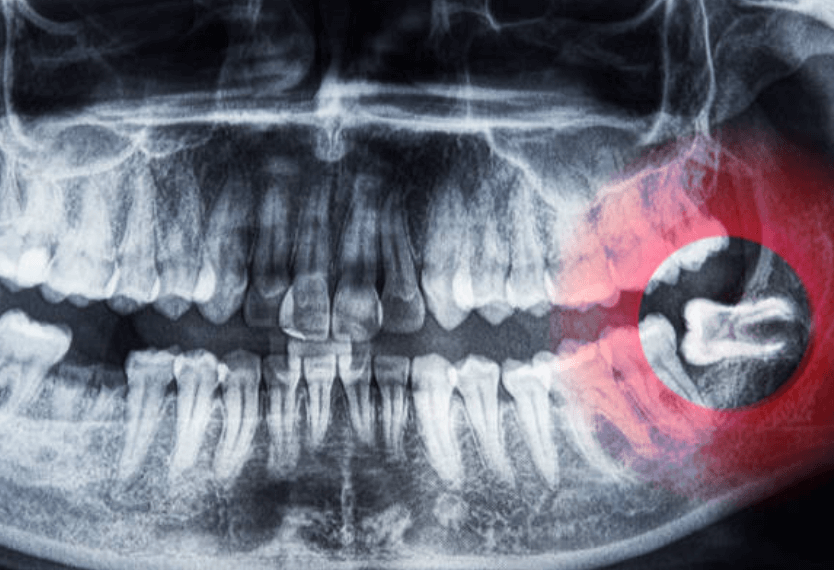

사랑니를 뽑으면 구멍이 생기는 것은 단순발치, 단순매복, 복잡 매복, 완전매복 등 케이스와 상관없이 무조건 생깁니다. 이빨을 뽑은 후에는 피가 채워지고 혈액 응고 작용으로 피가 굳어지는 과정을 거칩니다.

구멍에 음식물이 끼면 썩지 않을까 하는 걱정 때문에 이쑤시개나 손톱과 같은 뾰족한 물건으로 빼려고 하면 잇몸에 상처가 생길 위험이 있습니다. 또한 피떡이 떨어지는 날에는 세균이 침투해 합병증인 드라이 소켓을 유발할 수도 있습니다.

드라이 소켓(Dry socket)은 응고된 피가 떨어지거나 완전히 아물지 않아 발생하는 상황입니다. 드라이 소켓이 생기는 원인은 아직 밝혀지지 않았지만, 일부 환자들은 노력해도 해결되지 않을 수 있습니다.